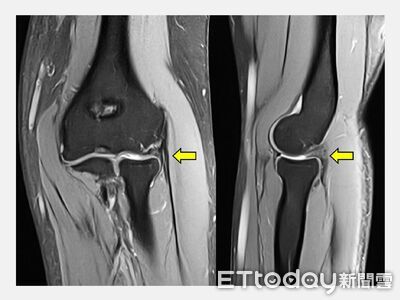

一名長時間伏案工作的35歲女會計師,3年前開始察覺右手肘外側不時傳來像被針刺般的痠痛。因身為會計師,每天與鍵盤、滑鼠為伍,原以為只是姿勢不良,休息一下就會好轉,沒想到疼痛逐漸頻繁,甚至連拿水杯、提資料袋都會一陣抽痛,讓她工作與日常生活大受影響。 《詳全文...》